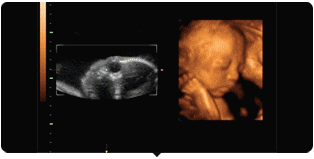

什么是四维彩超!

四维彩超就是四维成像技术(4D),能直观,立体显示人体器官的三维结构及动态、实时地观察立体结构。主要可以进行胎龄检测、分析胎儿的发育情况、筛查胎儿畸形等。

四维彩超动图欣赏

麻麻,我在咬手指哟!